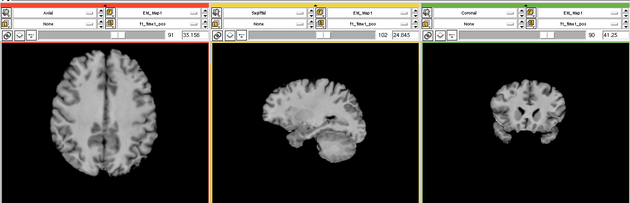

| + | Image:EMS LesionExp Segmentation.png | ||

Two channel automatic segmentation of T1 and FLAIR MRI brain scans into the major tissue classes (gray matter, white matter, csf). The pipeline consist of the following steps:

- Step 5: Automatically segment the MRI scan into the structures of interest using EM Algorithm (Pohl et al 2007)